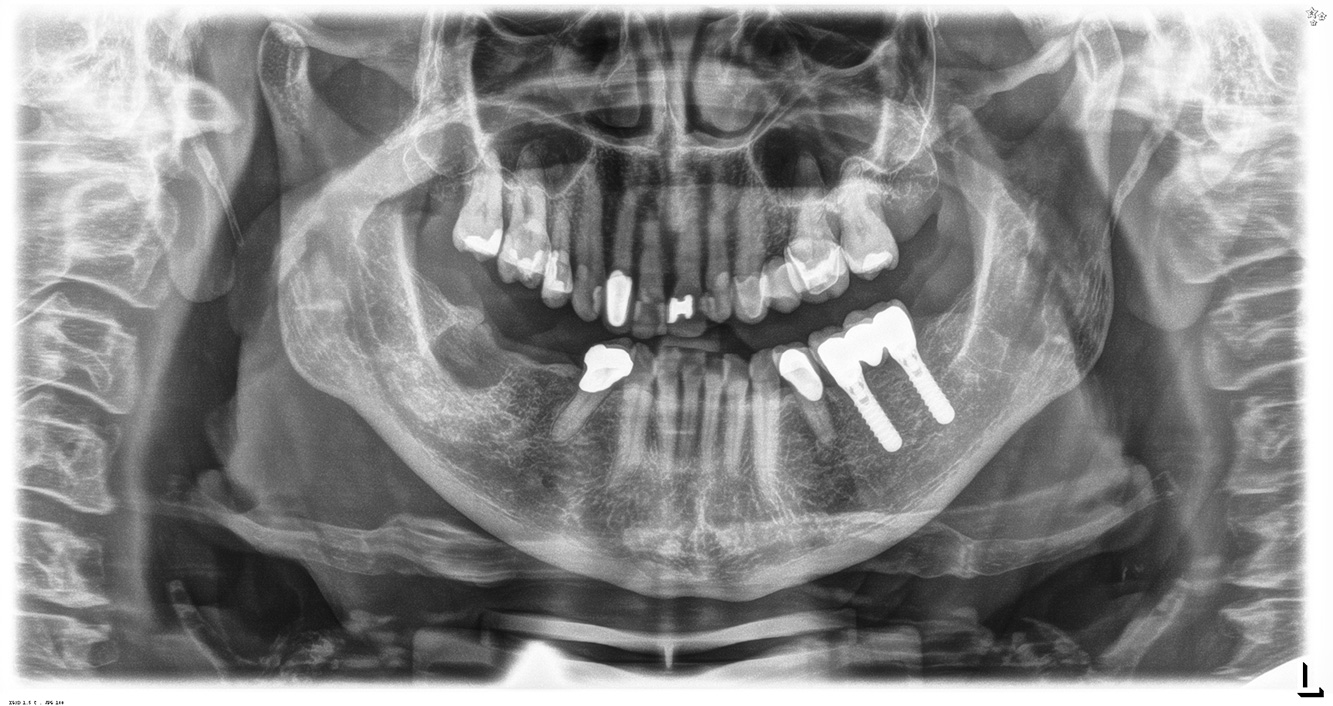

La paciente de 68 años no tiene enfermedades previas relevantes de la salud general ni toma medicación; sus hábitos alimentarios tampoco suponen un riesgo especial. La paciente tiene dos implantes (tercer cuadrante, desde hace cinco años) y una enfermedad previa periodontal (periodontitis en etapa IV, grado B) con pérdida dental. Actualmente las condiciones periodontales son estables, pero la periodontitis aumenta de manera determinante las complicaciones biológicas cuando se realizan implantes y puede ocasionar la pérdida de un implante (21). Para la sesión de profilaxis se hacen cuatro recomendaciones.